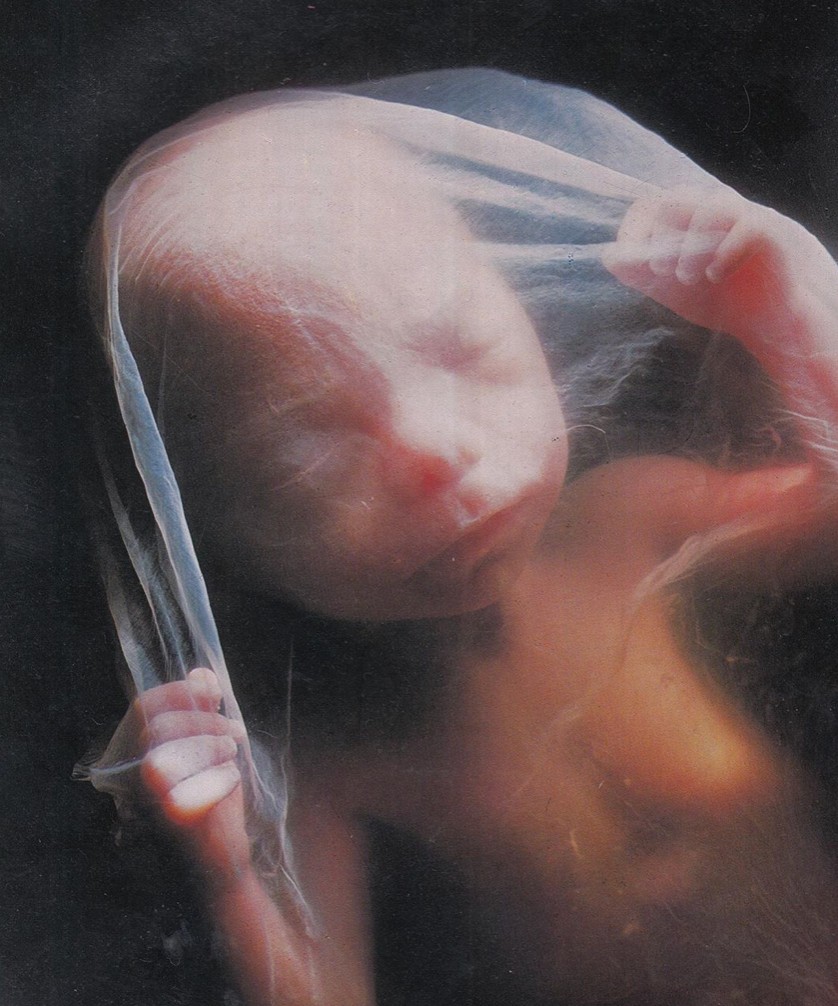

25 недель беременности: Как выглядит будущий малыш

Раздел: Образы вокруг